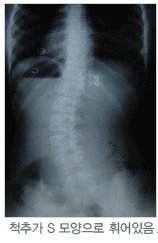

10대들의 적! 성장기 아이들에게 발생되는 질병은 척추측만증

척추측만증은 여러 가지 원인에 의해서 뒤에서 봤을 때 일자로 되어야 할 척추가

C자나 또는 S자로 휘어진 상태를 말하는데요~